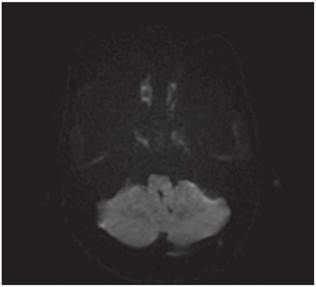

<p>Los estudios de hemograma, nitrógeno ureico, creatinina, glucemia y electrolitos se encontraron dentro de los rangos normales, el perfil lipídico mostró: colesterol total 160 mg/dl, colesterol HDL 50 mg/dl, colesterol LDL 89,8 mg/dl, triglicéridos 101 mg/dl. La tomografia de cráneo simple no mostró sangrado ni signos de isquemia. Se realizó una resonancia magnética cerebral simple que permitió evidenciar en las secuencias de T2 y FLAIR <italic>(Fluid Attenuation Inversion Recovery)</italic> una zona de hiperintensidad de señal a nivel del bulbo raquídeo en la región dorso-lateral caudal izquierda que es hipointensa en T1 (<xref ref-type="fig" rid="f1">figuras 1</xref>,<xref ref-type="fig" rid="f2">2</xref>,<xref ref-type="fig" rid="f3">3</xref>,<xref ref-type="fig" rid="f4">4</xref>). En la secuencia de difusión se observa restricción de la misma en la zona descrita con fenómeno de pseudonormalización al igual que en el mapa ADC <italic>(Apparent Coefficient Diffusion}</italic> (<xref ref-type="fig" rid="f5">figuras 5</xref>,<xref ref-type="fig" rid="f6">6</xref>). Los anteriores hallazgos se interpretaron como compatibles con un infarto bulbar lateral izquierdo.</p>

<p>El paciente se caracterizó por tener principalmente dis-fagia, disfonía, vértigo, ataxia y hemiparesia ipsilateral, las cuales rápidamente mejoraron, siendo llamativo la ausencia de nistagmo el cual se reporta en una incidencia importante. El estudio por resonancia magnética se logró realizar 1 semana posterior al inicio de los síntomas, lo cual generó la limitante de observar pseudo-normalización en la secuencia DWI (Diffusion Weighted Imaging) y por ende ausencia de una clara restricción de la difusión. En el T2 corte coronal se puede ver extensión hacia zonas caudales de la unión bul-bomedular, lo cual explicaría por qué presentó compromiso del tracto cortico-espinal siendo la primera causa, la lesión de las fibras ya decusadas provenientes del hemisferio contrala-teral ya sea por isquemia o por efecto de masa por el edema adyacente, este hallazgo se correlaciona con lo mayormente reportado en otras publicaciones. Un elemento importante en el paciente fue el inicio súbito de los síntomas posterior a realizar una rotación brusca del cuello con dolor cervical asociado, lo cual debe ubicar al clínico en un contexto cuya principal etiología a estudiar sea la disección cervical dada además la ausencia de factores de riesgo cardiovasculares y la edad cercana a los 50 años, sin embargo, en una angiografía convencional tomada 3 semanas después, no se evidenció esta etiología según lo informado por radiología. A pesar del compromiso motor, no todos los pacientes que cursan con síndrome de Opalski tienen una afectación marcada de la funcionalidad e independencia <xref ref-type="bibr" rid="B17"><sup>17</sup></xref> y la debilidad evidenciada es leve y transitoria permitiendo su recuperación hasta el 100 % previo, como se observó en este caso. Por otro lado, es importante evitar complicaciones tempranas como la broncoaspiración y neumonitis secundaria y, por ende, se hace imperativo plantear desde el ingreso de estos pacientes una vía alterna de alimentación a través de sonda naso u orogástrica o gastrostomía mientras se lleva a cabo el proceso de rehabilitación de la disfagia de forma paralela.</p>